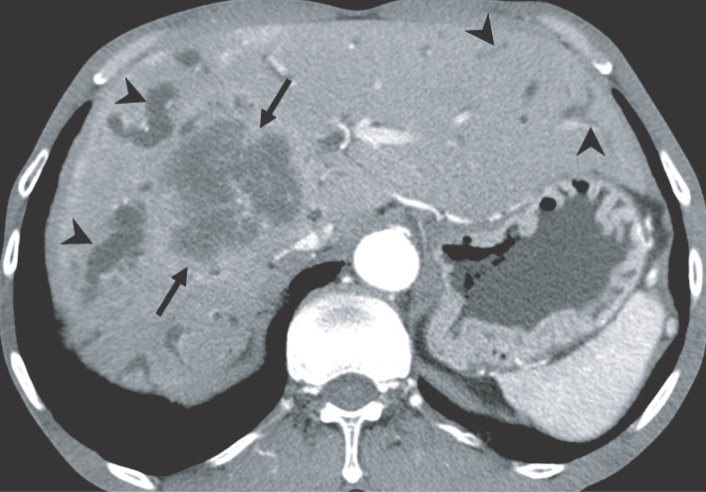

Fig. 5

Cholangiocarcinoma in the right hepatic lobe, with clonorchiasis, in a 63-year-old man. There is diffuse dilatation of peripheral intrahepatic bile ducts (arrowheads) is attributed to changes of a C. sinensis infection, and segmental and more severe dilatation around the tumor is caused by obstruction by the tumor (arrows).

Fig. 5 Cholangiocarcinoma in the right hepatic lobe, with clonorchiasis, in a 63-year-old man. There is diffuse dilatation of peripheral intrahepatic bile ducts (arrowheads) is attributed to changes of a C. sinensis infection, and segmental and more severe dilatation around the tumor is caused by obstruction by the tumor (arrows).

The imaging findings of clonorchiasis-associated cholangiocarcinomas are combinations of the findings of the 2 diseases (Figs. 5 and 6) (Choi et al., 2004). Diffuse dilatation of peripheral intrahepatic ducts is attributed to changes that are secondary to clonorchiasis, and segmental and severe dilatation around the tumor is caused by obstruction by the tumor (Fig. 5) (Choi et al., 1988 & 1989). Extrahepatic cholangiocarcinomas, associated with clonorchiasis, show diffuse dilatation of the peripheral and central intrahepatic bile ducts (Fig. 6). When an extrahepatic cholangiocarcinoma is not associated with clonorchiasis, dilatation of the peripheral intrahepatic bile ducts is not conspicuous (Fig. 7). After the development of the distal obstruction due to an extrahepatic cholangiocarcinoma, pre-existent dilated intrahepatic bile ducts with clonorchiasis easily progress the dilatation.